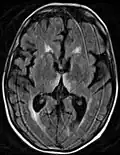

Axial MRI FLAIR image showing hyperintense signal in the mesial dorsal thalami, a common finding in Wernicke encephalopathy. This patient was nearly in coma when IV thiamine was started, he responded moderately well but was left with some Korsakoff type deficits. -

Axial MRI B=1000 DWI image showing hyperintense signal indicative of restricted diffusion in the mesial dorsal thalami -

Axial MRI FLAIR image showing hyperintense signal in the periaqueductal gray matter and tectum of the dorsal midbrain